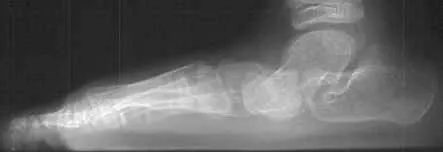

Flatfoot is common in both children and adults. When this deformity occurs in children, it is referred to as “pediatric flatfoot.” Although there are various forms of flatfoot, they all share one characteristic – partial or total collapse of the arch.

X-rays are often taken to determine the severity of the deformity. Sometimes additional imaging and other tests are ordered.